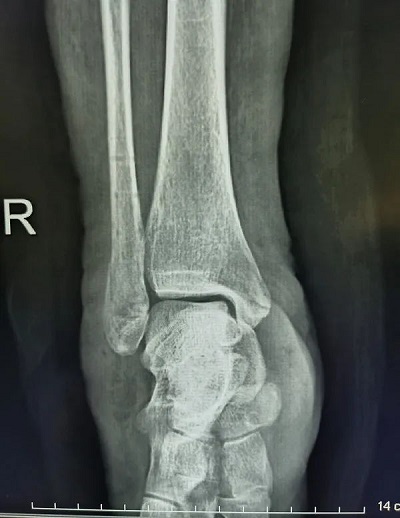

患者柯某某,女,58 岁,因外伤致右踝关节损伤,入院诊断为右内外踝骨折伴踝关节脱位,受伤后踝关节肿胀明显,给予系统性治疗,6天后消肿,手术前手足显微外科室多次讨论、综合评估、完善术前准备,制定了详细手术方案。由于担心自己年龄较大,患者不想二次进行手术取出金属内固定,选择可吸收钉板进行手术。在麻醉科的配合下用时近2小时左右顺利完成手术,术后拍片显示骨折及关节达到临床复位。

右内外踝骨折伴踝关节脱位术前